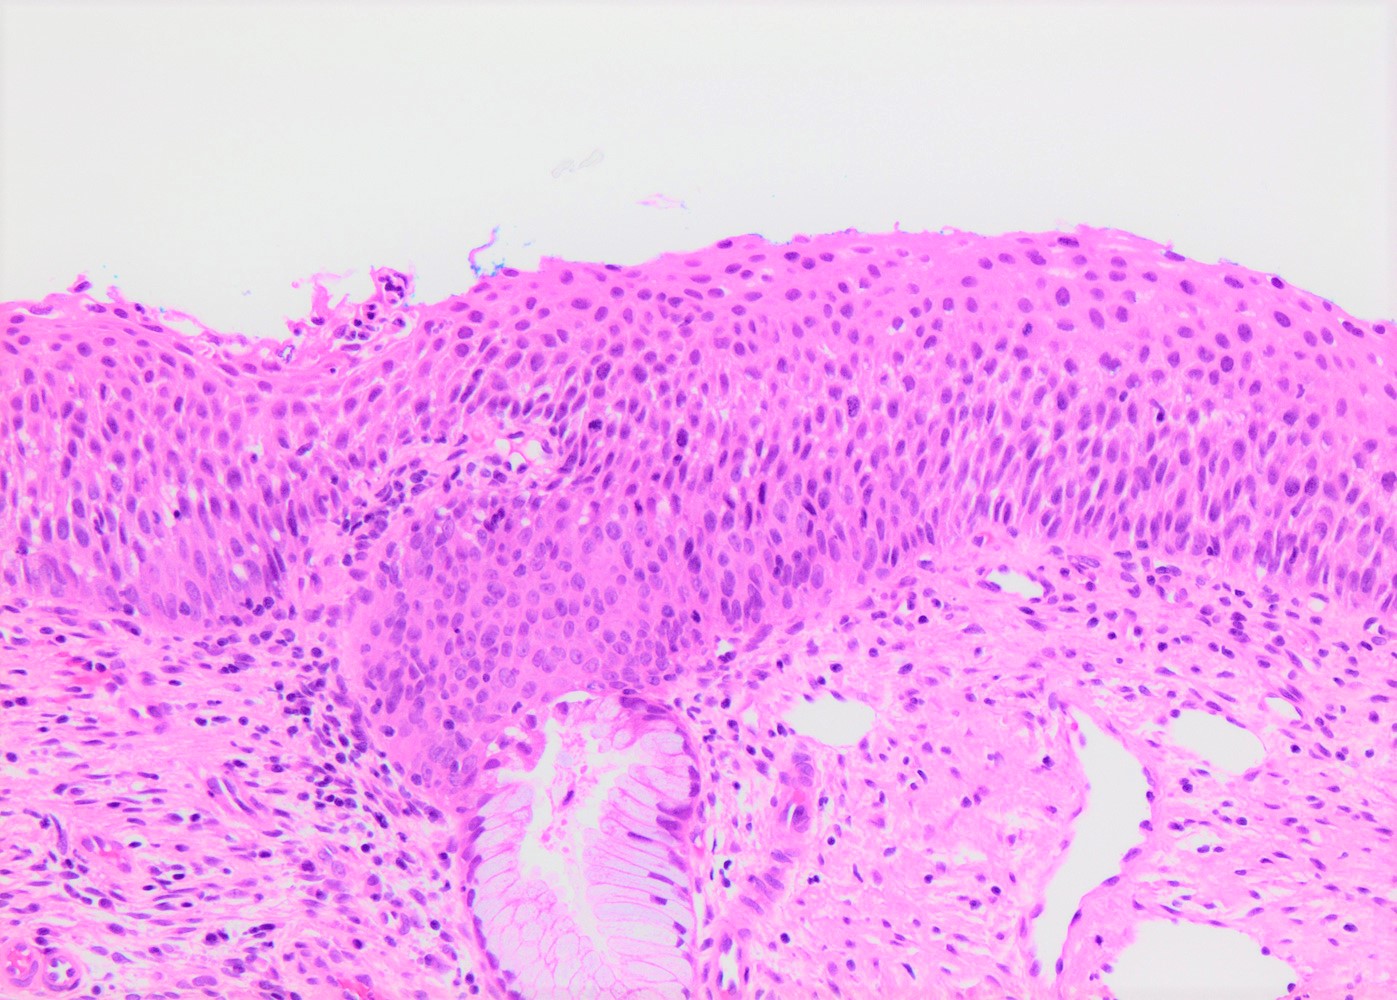

- Conventional / classic pattern: full thickness nuclear abnormalities (hyperchromasia, coarse chromatin, irregular nuclear contours and inconspicuous nucleoli), high N/C ratio in at least lower two - thirds of epithelium

- CIN II: cytoplasmic maturation in the upper third of mucosa

- CIN III: full thickness basal / parabasal type, no maturation difference across layers

- Increased mitotic activity with atypical mitoses

Microscopic (histologic) images

Contributed by Khaled J. Alkhateeb, M.B.B.S.

A 32 year old woman presented after 2 consecutive Pap tests revealing atypical squamous cells of undetermined significance (ASCUS). Colposcopic exam was unsatisfactory. Loop electrosurgical excision procedure (LEEP) was performed and showed the histologic findings in the image above. What immunohistochemical study and staining pattern combination would be expected in this lesion?